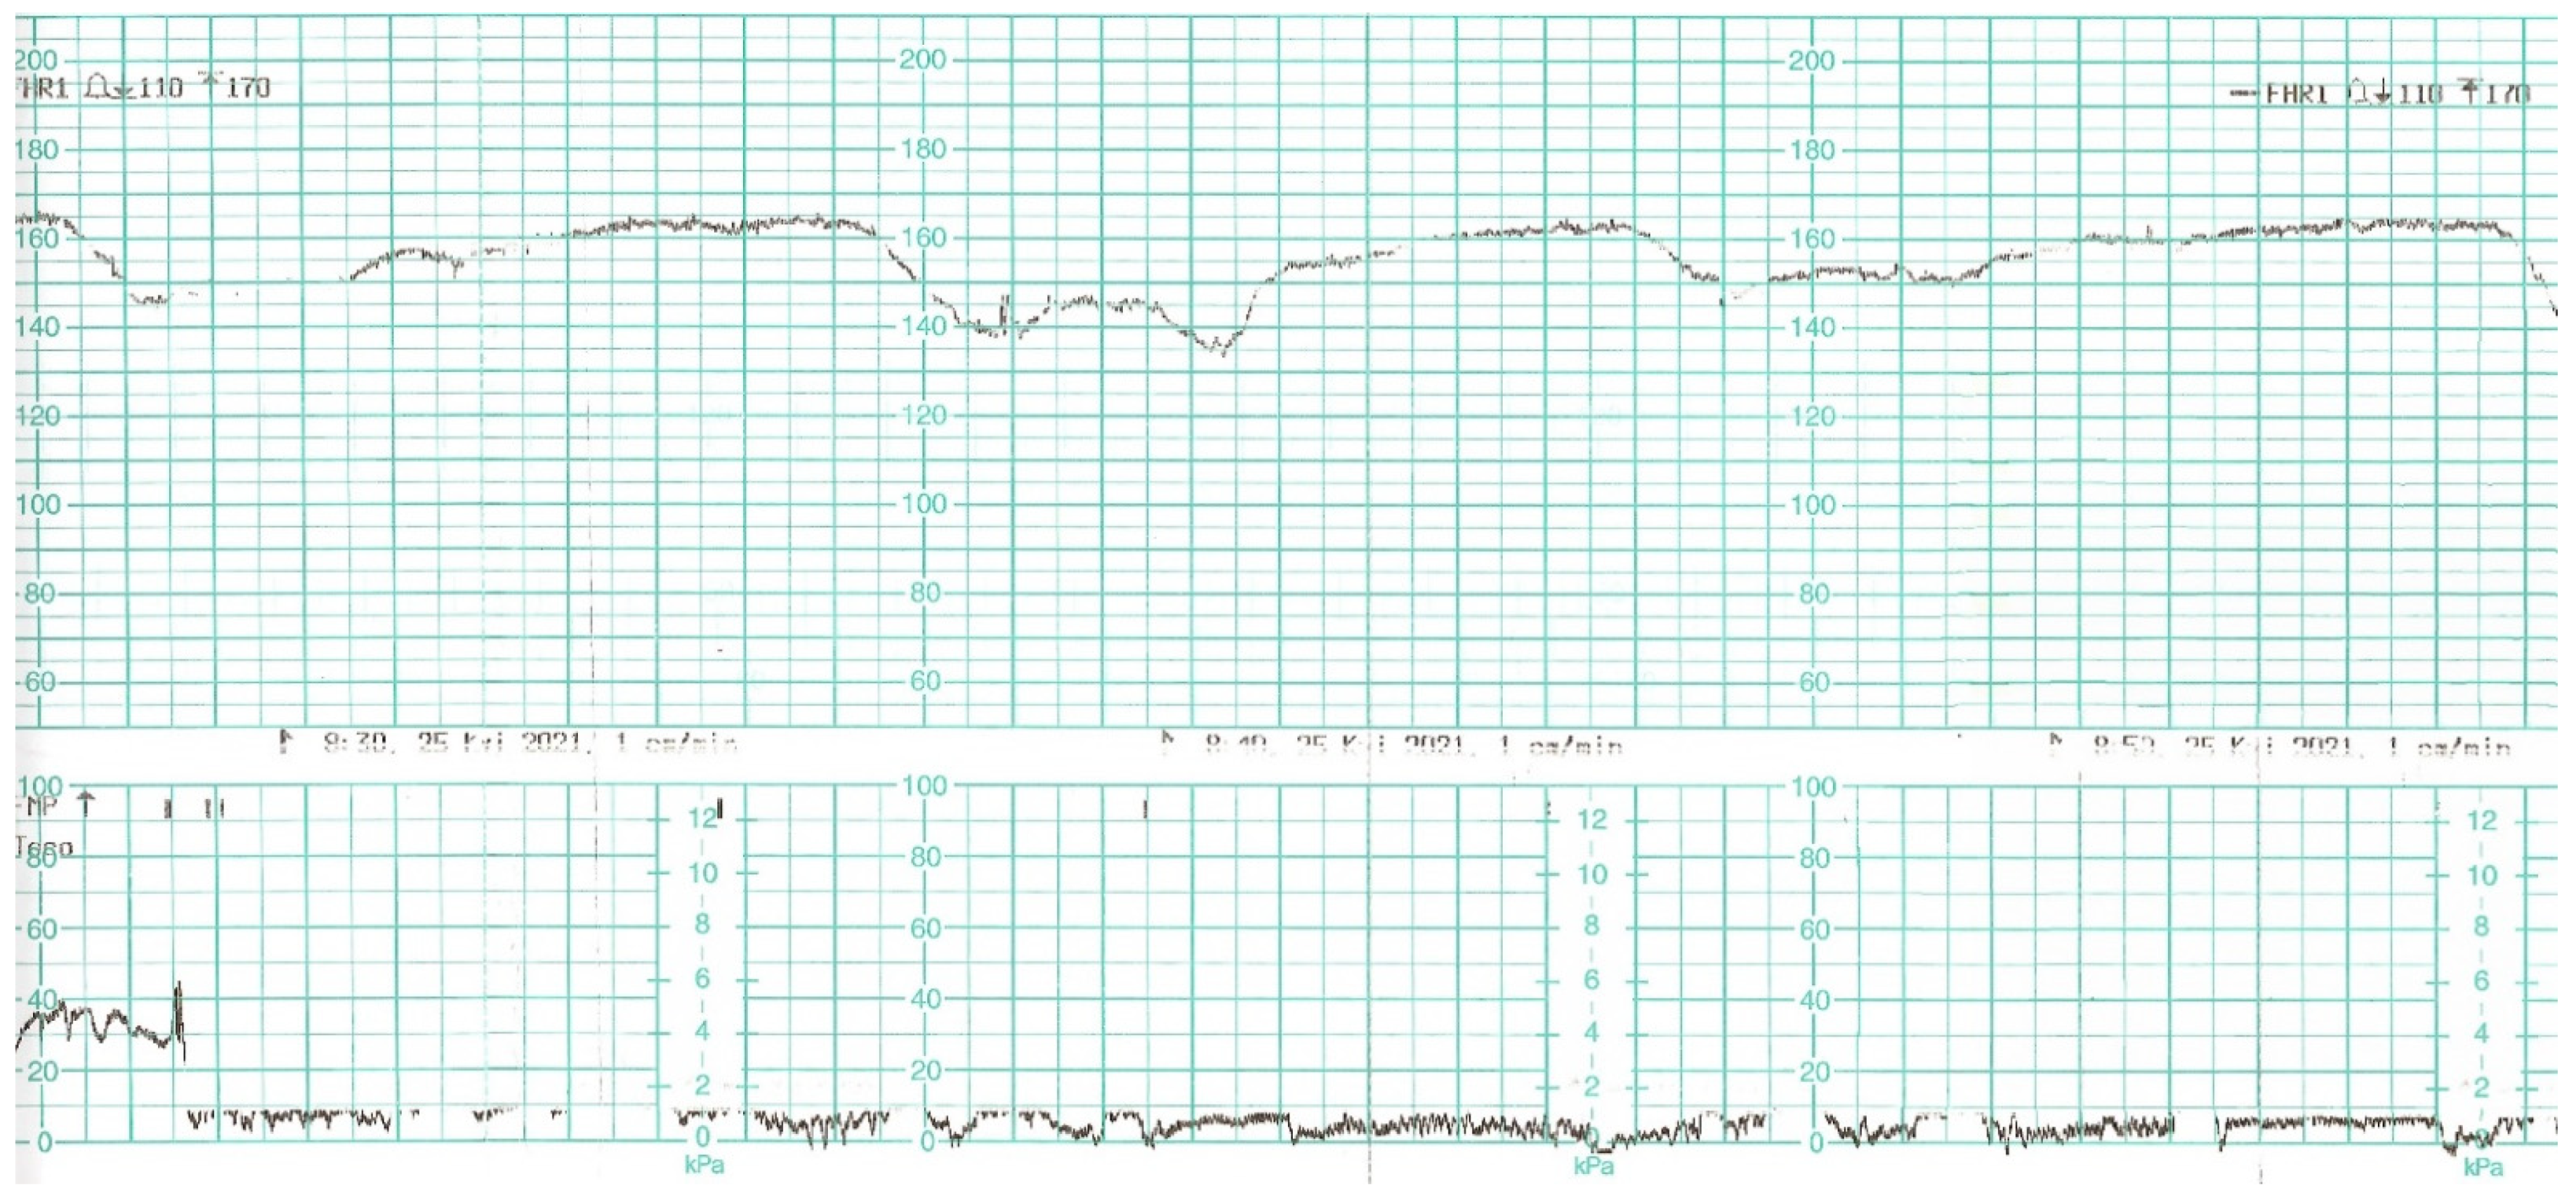

While waiting for the results of laboratory tests, a control cardiotocographic (CTG) recording was made. During the CTG recording, the foetal heart rate was found between 140 and 160 bpm. Within approximately 25 min of recording, reduced short-term variability with single decelerations and no acceleration was found—a pathological record that may suggest foetal hypoxia (Figure 1).

Figure 1.

Cardiotocography recording in a patient 1—normal baseline, reduced variability.